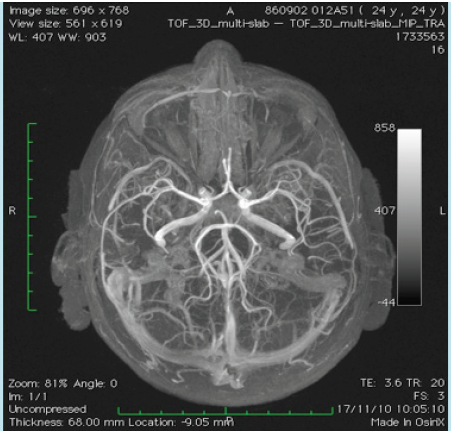

The mother and grandmother had also frequent nosebleeds with the presence of telangiectesia at the levels of the lips, tong, fingers and stomach. These findings were absent in our presented patient. The magnetic resonance (MR) angiography of the brain showed no arteriovenous malformations (Figure 1). On MR imaging a small bleed was observed in the right superior colliculus at the level of the mesencephalon (Figure 2). Also a small bleed was detected in the left anterior paramedian part of the pons (Figure 3).

Figure 1 Magnetic resonance imaging with angiography of the circulus of Willis and its afferent arteries. No arteriovenous malformations are detected.